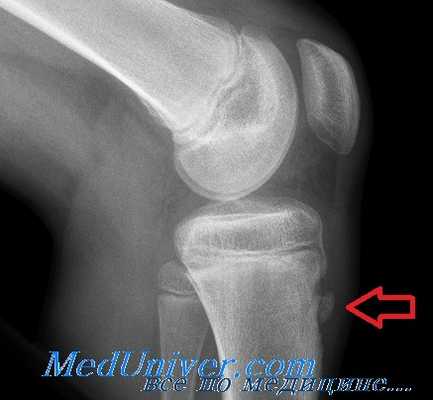

Основным методом инструментальной диагностики является рентген коленных суставов в двух проекциях, который позволяет увидеть структурные изменения бугристости [4] .

Фрагментацию с отрывом костного фрагмента лучше всего видно на боковой рентгенограмме [10] .

Рентгенологически отмечается характерная картина для этого заболевания. У молодых людей, когда еще не закрылась зона роста, видны неслившийся апофиз бугристости и отдельные костные фрагменты. Часто можно видеть значительную деформацию бугристости в виде «хобота». У более старших танцовщиков эта бугристость может иметь вид отдельных костных фрагментов.